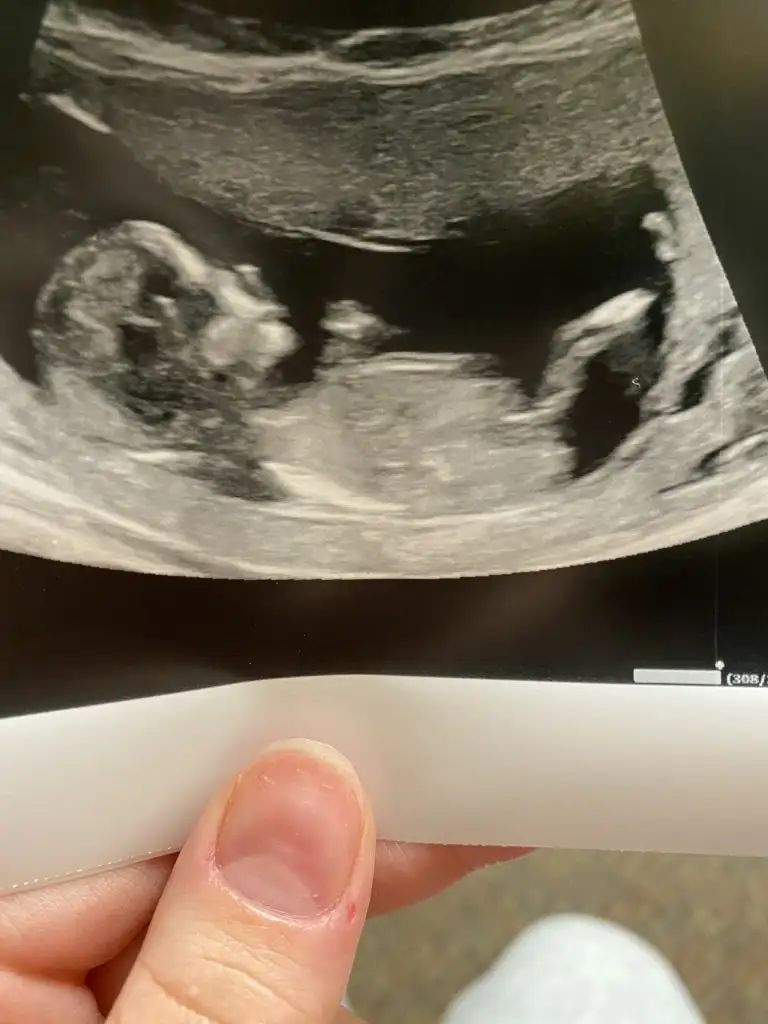

Çok tesekkur ederim zahmet olmasa buna da bakabilir misiniz kardesimin 8 haftalikBuna göre kızama siz 11 12 13 hafta nub için paylaşın

Buda kız yolksac göre bakıyorumÇok tesekkur ederim zahmet olmasa buna da bakabilir misiniz kardesimin 8 haftalik